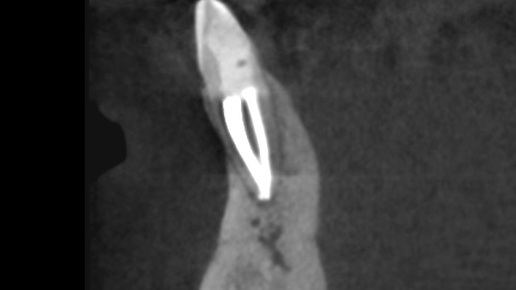

Я уже рассказывала, как сама чуть не лишилась двойки на нижней челюсти из-за неправильных действий коллег. Во времена интернатуры/ординатуры целёхонький зуб без кариеса (интактный) затавил меня побегать по потолку и по врачевателям зубовным. И что? Заметили проблему, вылечили? Шиш. Отдал несчастный душу фее зубной, упокоился и успокоился, шишка толко прощальная на десне вскочила, в проекции которой сделали разрез и отпустили с миром - ну конечно, так же лечатся больные зубы. Нет, не так. Опытные...